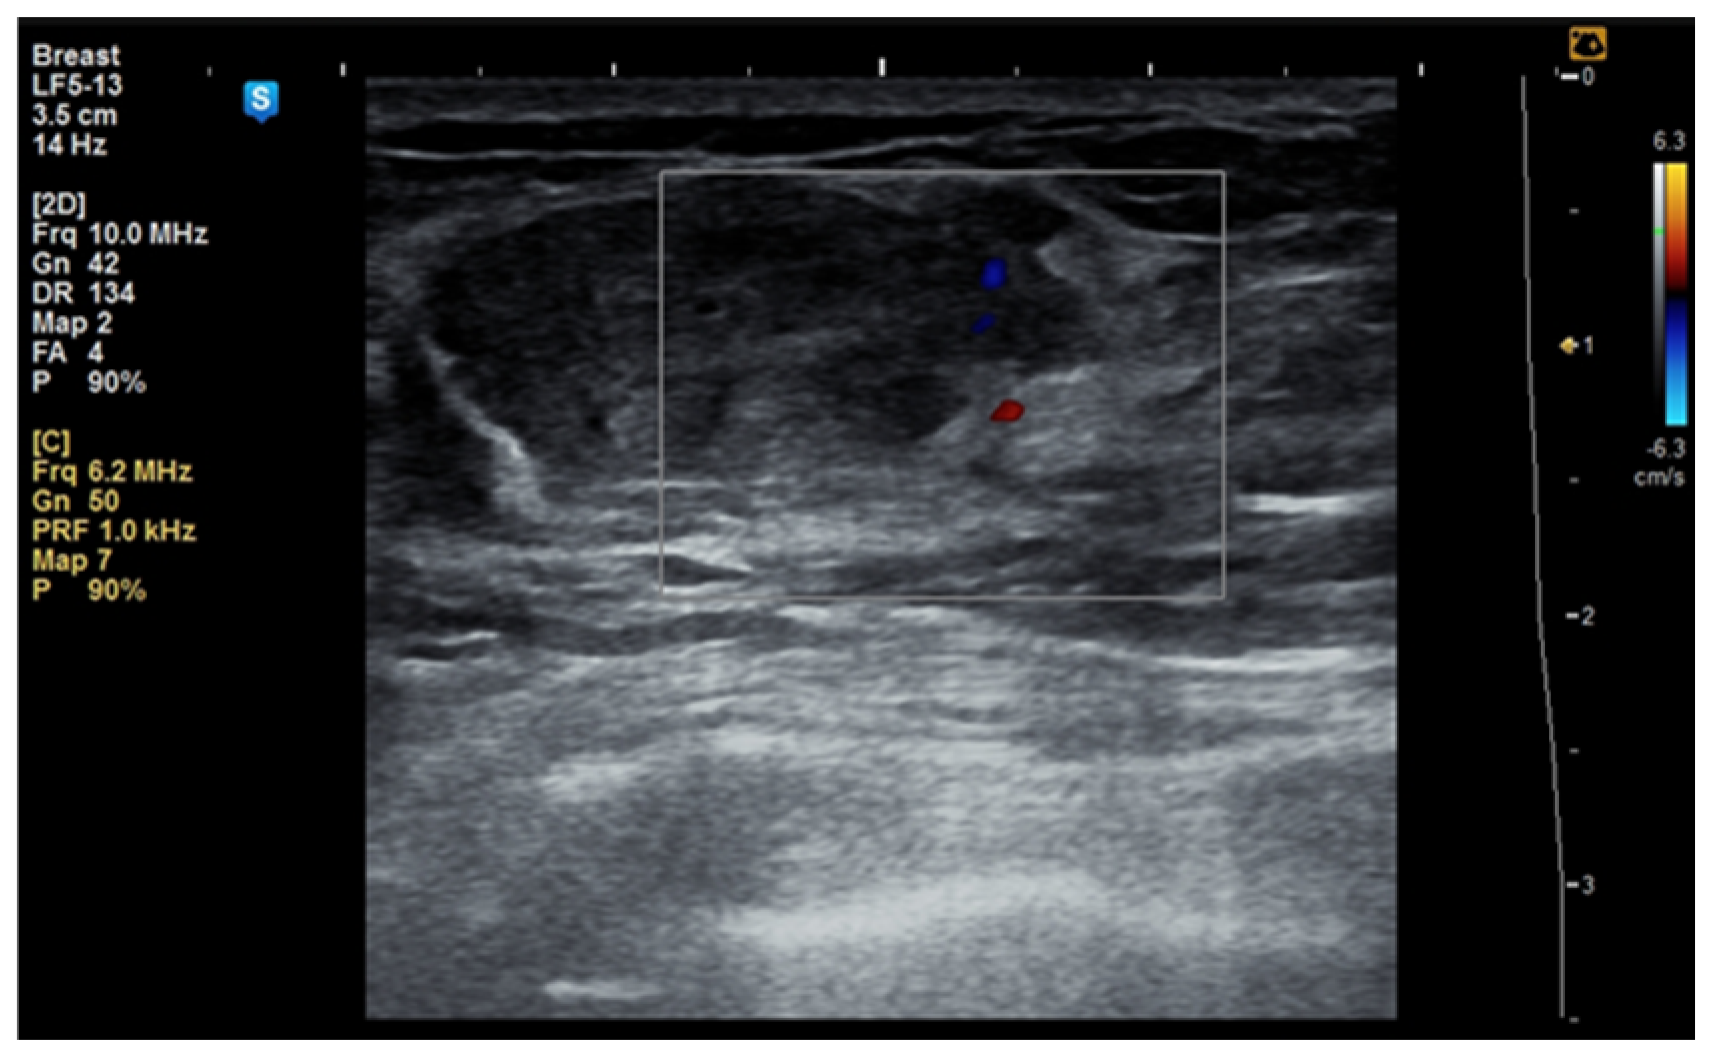

In some cases, the diagnosis was initially suspected to be a malignant tumor (Figure 3a–c).

Figure 3.

A 53-year-old woman with a tumor in the right upper outer mammary quadrant (a) with predominant hyperechoic structure; (b) with a peripheral vessel; (c) with benign axillary adenopathy.